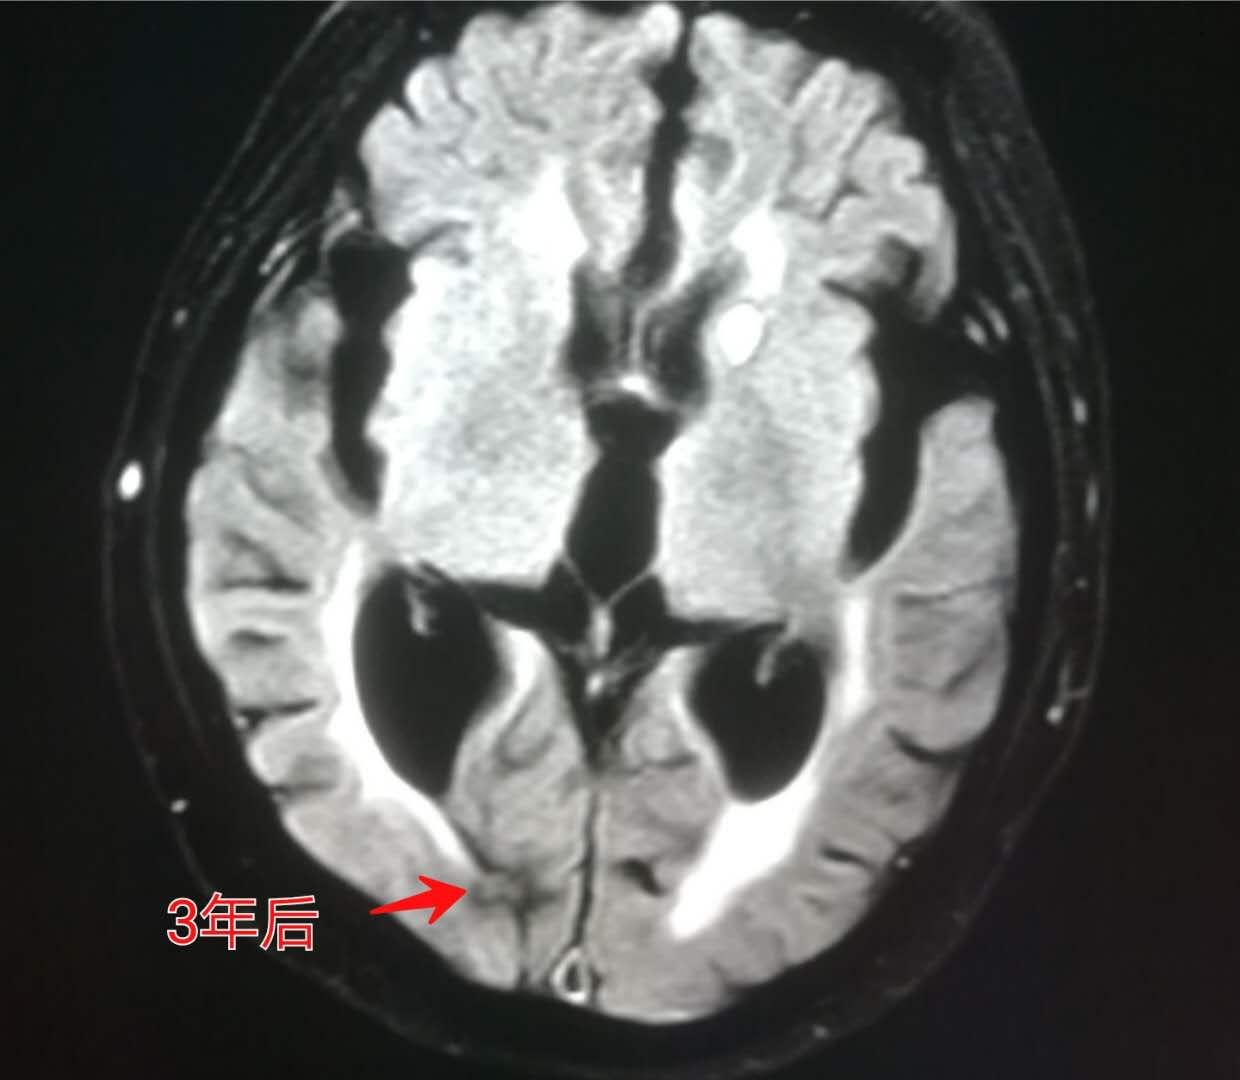

上图这位老人就是因为视物模糊,脑部核磁共振(MR)发现脑转移瘤。

上面提到那位视力模糊的老人,做了脑部放疗和肺部化疗,3年后复查,脑转移瘤明显萎缩。